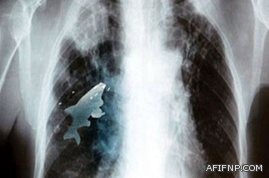

وقد تسبب ذلك في تدهور صحته وشعوره بالاختناق وبألم في الصدر، مما استدعى تصوير صدره بالأشعة مما كشف وجود جسم متحرك داخل رئته.

وتم إخضاعه لمزيد من الفحوص بواسطة جهاز الماسح الضوئي اتضح أنها سمكة حية وما زالت تتحرك داخل رئته اليمنى.